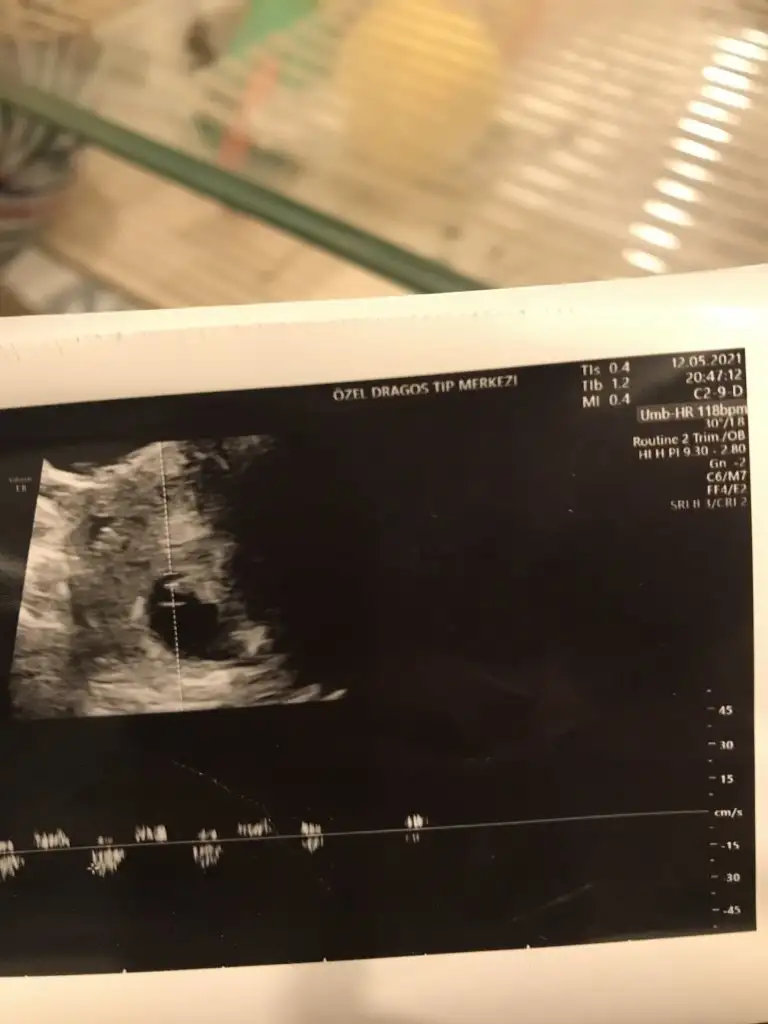

Bana da bakar misiniz ilki 6+4 vajinal diger ikisi 12+5 karindan cinsiyet belli degil henuz tahmin ederseniz sevinirim